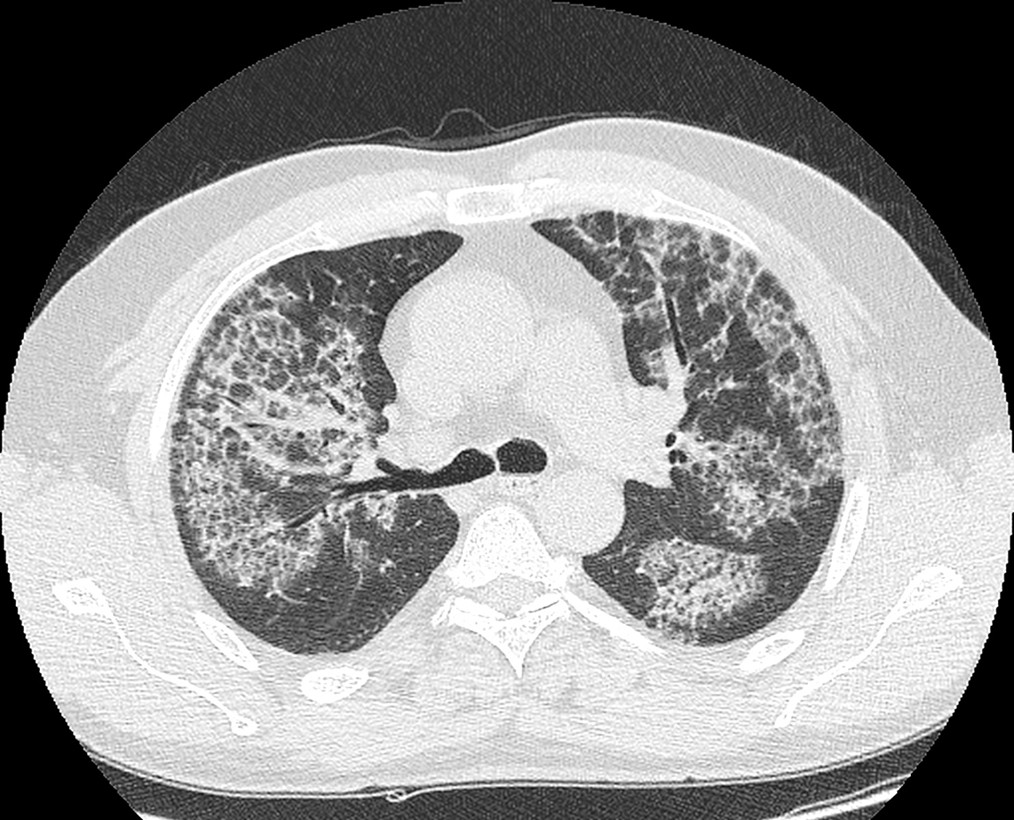

Przedstawiony powyżej obraz KT najbardziej przypomina obraz spotykany w:

1) włóknieniu śródmiąższowym płuc; 4) lipoproteinozie;

2) histiocytozie X; 5) ARDS.

3) krwawieniu śródpęcherzykowym;

Prawidłowa odpowiedź to: